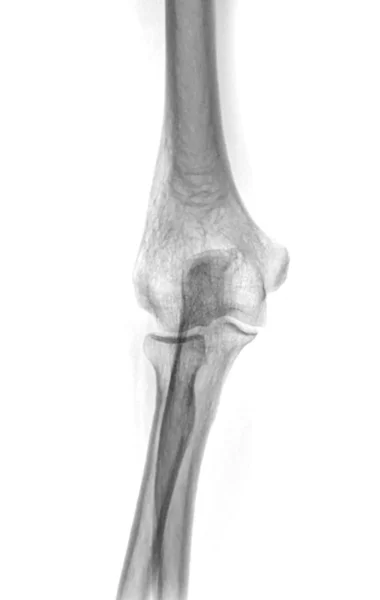

Frattura olecrano destro. An olecranon fracture is a break in the bony tip of the elbow. An olecranon fracture is a break at the base of the elbow joint. La frattura dellolecrano provoca dolore a livello del gomito grave limitazione del movimento ematomi e gonfiore.

In altri termini. An olecranon oh-LEK-rah-nun fracture is a break in the bony tip of the elbow. The olecranon is a large bony prominence at the proximal end of the ulna.

An olecranon fracture can occur through a. It is palpable at the posterior aspect of the elbow. Frattura dellolecrano Le fratture dellolecrano Fig1 interessano lestremità superiore dellulna.

Because the olecranon is positioned directly under the skin with little protection from muscles or other soft tissues it can break easily if you experience a blow to the elbow or fall on an outstretched arm. Figure 1 Olecranon Fracture Anatomy. Dolore e tempi di guarigione.

An olecranon fracture is a relatively uncommon condition characterized by a break in the bony prominence situated at the back of the elbow known as the olecranon figure 1. Il 2 agosto ho subito un trauma che mi ha causato la fratura dellolecrano destro. This type of fracture is common and usually occurs in isolation there are no other injuries but can also be a part of a more complex elbow injury.